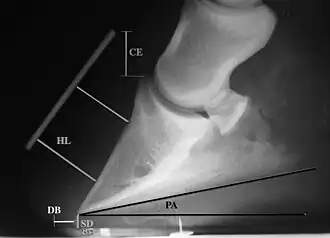

Radiographic measurements

Radiographic measurements, including coronary extensor distance (CE), horn:lamellar distance (HL), sole depth (SD), digital breakover (DB), and palmar angle (PA)

Several radiographic measurements, made on the lateral view, allow for objective evaluation of the episode.

1. Coronary extensor distance (CE): the vertical distance from the level of the proximal coronary band to the extensor process of P3. It is often used to compare progression of the disease over time, rather than as a stand-alone value. A rapidly increasing CE value can indicate distal displacement (sinking) of the coffin bone, while a more gradual increase in CE can occur with foot collapse. Normal values range from 0–30 mm, with most horses >12–15 mm.[1]

2. Sole depth (SD): the distance from the tip of P3 to the ground.

3. Digital breakover (DB): distance from the tip of P3 to the breakover of the hoof (dorsal toe).[1]

4. Palmar angle (PA): the angle between a line perpendicular to the ground, and a line at the angle of the palmar surface of P3.

5. Horn:lamellar distance (HL): the measurement from the most superficial aspect of the dorsal hoof wall to the face of P3. 2 distances are compared: a proximal measurement made just distal to the extensor process of P3, and a distal measurement made toward the tip of P3. These two values should be similar. In cases of rotation, the distal measurement will be higher than the proximal. In cases of distal displacement, both values will increase, but may remain equal. Therefore, it is ideal to have baseline radiographs for horses, especially for those at high-risk for laminitis, to compare to should laminitis ever be suspected. Normal HL values vary by breed and age:[1]